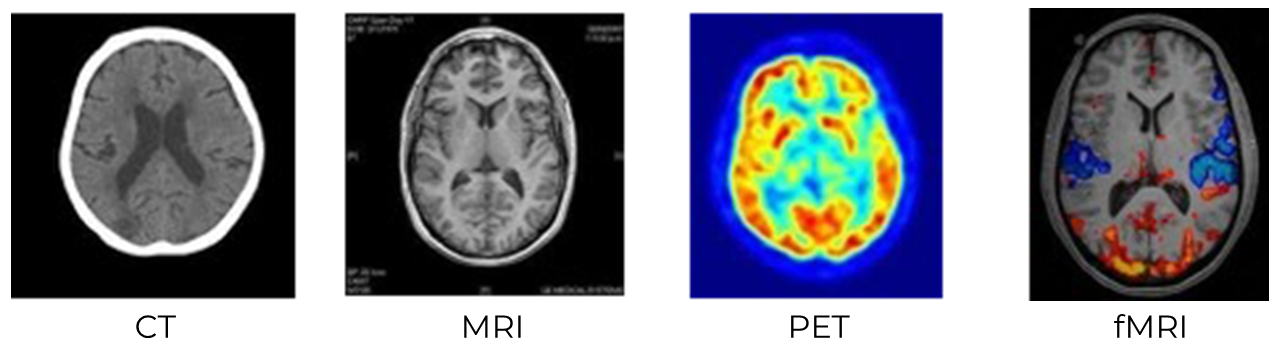

In order to activate students’ observational skills, ask them to analyze the images below of different technical brain imaging methods.

Explain that there are many different ways to get a visual representation of what is going on inside the head. Each method has strengths and weaknesses, and because of this, certain methods are typically used in certain settings.

Show students the images below and ask the the questions that follow:

Image- Ask students to answer the following questions independently:

- Which images are the sharpest? Which are the fuzziest?

- Which images have intensity or color scales? What do you think the colors or intensities might signify in each image?

- Compare the CT/MRI images with the PET/fMRI. What differences and similarities do they see between these groups?

- If students point out that MRI and fMRI look sharper than CT and PET, explain that the date of development of each technology correlates with the increasing image resolution. CT was introduced in the early 1970s, PET and MRI in the 1980s, and fMRI in the 1990s. Most present-day research in cognitive neuroscience uses fMRI when looking at brain activity for this very reason.

- If students point out that CT doesn’t show the difference between the white matter and gray matter within the brain, you can explain that this is why CT is not commonly used for neuroscience experiments but is often used by doctors and hospitals to see the location of tumors or areas of damage within the brain. Refer to Unit 1, Lesson 5 for more on gray and white matter.